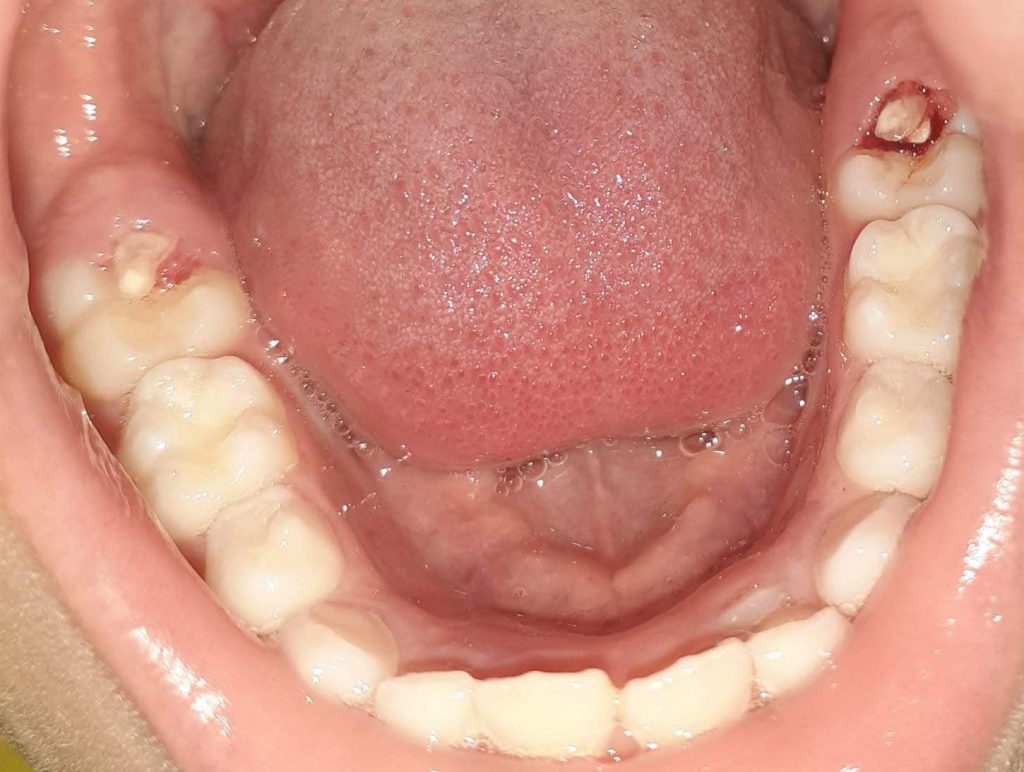

Bone fragments after tooth extraction (sequestra). Tooth pieces. Removal Pictures Tooth Dental Bone Sequestra After a tooth extraction or other dental procedure, this bone fragment may feel like a sharp bone sticking out of your gums or an uncomfortable object creating pressure. What is a dental sequestra? This is your body’s way of removing extra bone from the tooth extraction site. Dental bone spurs (also known as bone spicules) are small bone pieces that. Dental Bone Sequestra.

Dental sequestrum I pulled out 2.5 months postop from infected wisdom tooth extraction site r Dental Bone Sequestra Some dentists may refer to these as bone sequestra. Dental bone spurs (also known as bone spicules) are small bone pieces that become dislodged from the surrounding tissue but are still trapped in your gums. After a tooth extraction or other dental procedure, this bone fragment may feel like a sharp bone sticking out of your gums or an uncomfortable. Dental Bone Sequestra.

Lingual sharp exposed painful bony dehiscence sequestrectomy from wisdom teeth extraction Dental Bone Sequestra A bone spur in the gum is also known as exostosis, a bone sequestra, or a bone spicule. It is essential to maintain good oral hygiene to. After a tooth extraction or other dental procedure, this bone fragment may feel like a sharp bone sticking out of your gums or an uncomfortable object creating pressure. This is your body’s way. Dental Bone Sequestra.